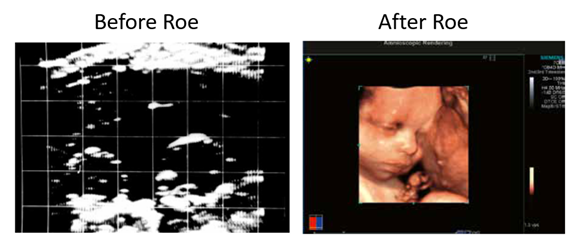

The black & white dots of an ultrasound before Roe could barely identify the head of an unborn child in the womb, much less identify the heartbeat at six weeks, show the child sucking his thumb at 15 weeks, or display her eyes, nose, lips, and behaviors with absolute clarity.